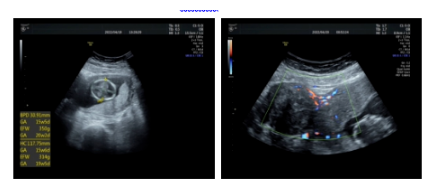

现病史:患者孕6周超声提示子宫肌瘤直径约5cm,孕10周肌瘤直径约7cm,孕12周肌瘤直径约9cm。患者1周前出现腹痛,改变体位可缓解,1天前出现剧烈腹痛不缓解,无伴随症状。

辅助检查:超声(2022-04-19)宫内孕活胎,羊水最大深度38mm,估计胎儿体重135g。宫颈管闭合段长度36.1mm。

超声(2022-04-20)子宫右侧实性肿物——浆膜下肌瘤变性?